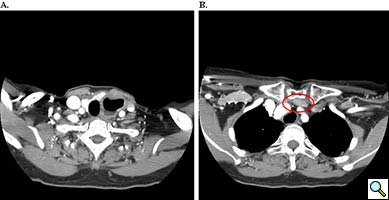

A 67 year old patient with a history of transhiatal esophagectomy (THE) and sub-sternal gastric pull-up ten years prior, at another institution, for early stage esophageal cancer presented with progressive dysphagia to solids. An initial esophagogastroduodenoscopy (EGD) found a large retained food bolus as well as tortuosity and dilatation of the cervical esophagus proximal to the esophagogastric anastomosis. No evidence of intrinsic anastomotic stricture or fibrosis was noted, but there was extrinsic compression. A barium esophagogram revealed significant extrinsic compression of the upper esophagus in the area of the anastomosis at the left clavicular head, with associated narrowing of the lumen and minimal transit of oral contrast (Figure 1). A computed tomography scan of the neck confirmed the sub-sternal location of the gastric pull-up within the anterior mediastinum, and revealed dilatation of the esophagus proximal to the anastomosis, with no associated masses or disease recurrence (Figure 2). The left sternoclavicular joint (SCJ) appeared to be compressing the conduit and was the point of obstruction.

To rule out anastomotic malignant recurrence, a flexible EGD was again performed with fluoroscopic guidance and four quadrant biopsies were taken off the distal cervical esophagus and the proximal gastric conduit. Fluoroscopy confirmed the intraluminal narrowing corresponded to the anatomic location of the left SCJ. The esophageal biopsies revealed squamous epithelium with no evidence of metaplastic, dysplastic, or neoplastic changes and the gastric conduit biopsies were benign as well. Given the absence of recurrent malignancy, the source of the extrinsic compression seen in the imaging of the patient’s cervical esophagogastric anastomosis was secondary to compression by her left SCJ. The patient elected to have the left SCJ resected due to ongoing worsening dysphagia.